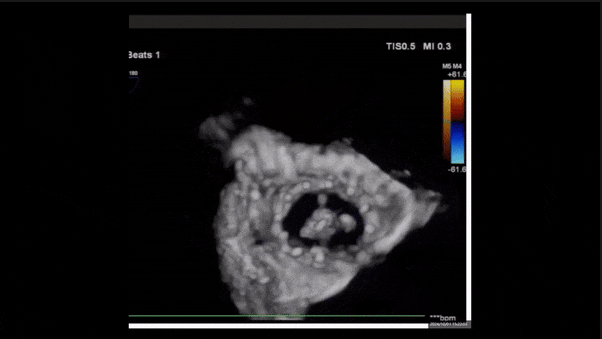

術后即刻返流三維

術后三維超聲

術后即刻經食道超聲可見,三尖瓣假體瓣膜位置合適,牛心包瓣葉運動狀態良好,開閉正常,瓣周及瓣葉對合緣處未見明顯返流,心電圖及心包狀態較術前無明顯變化。